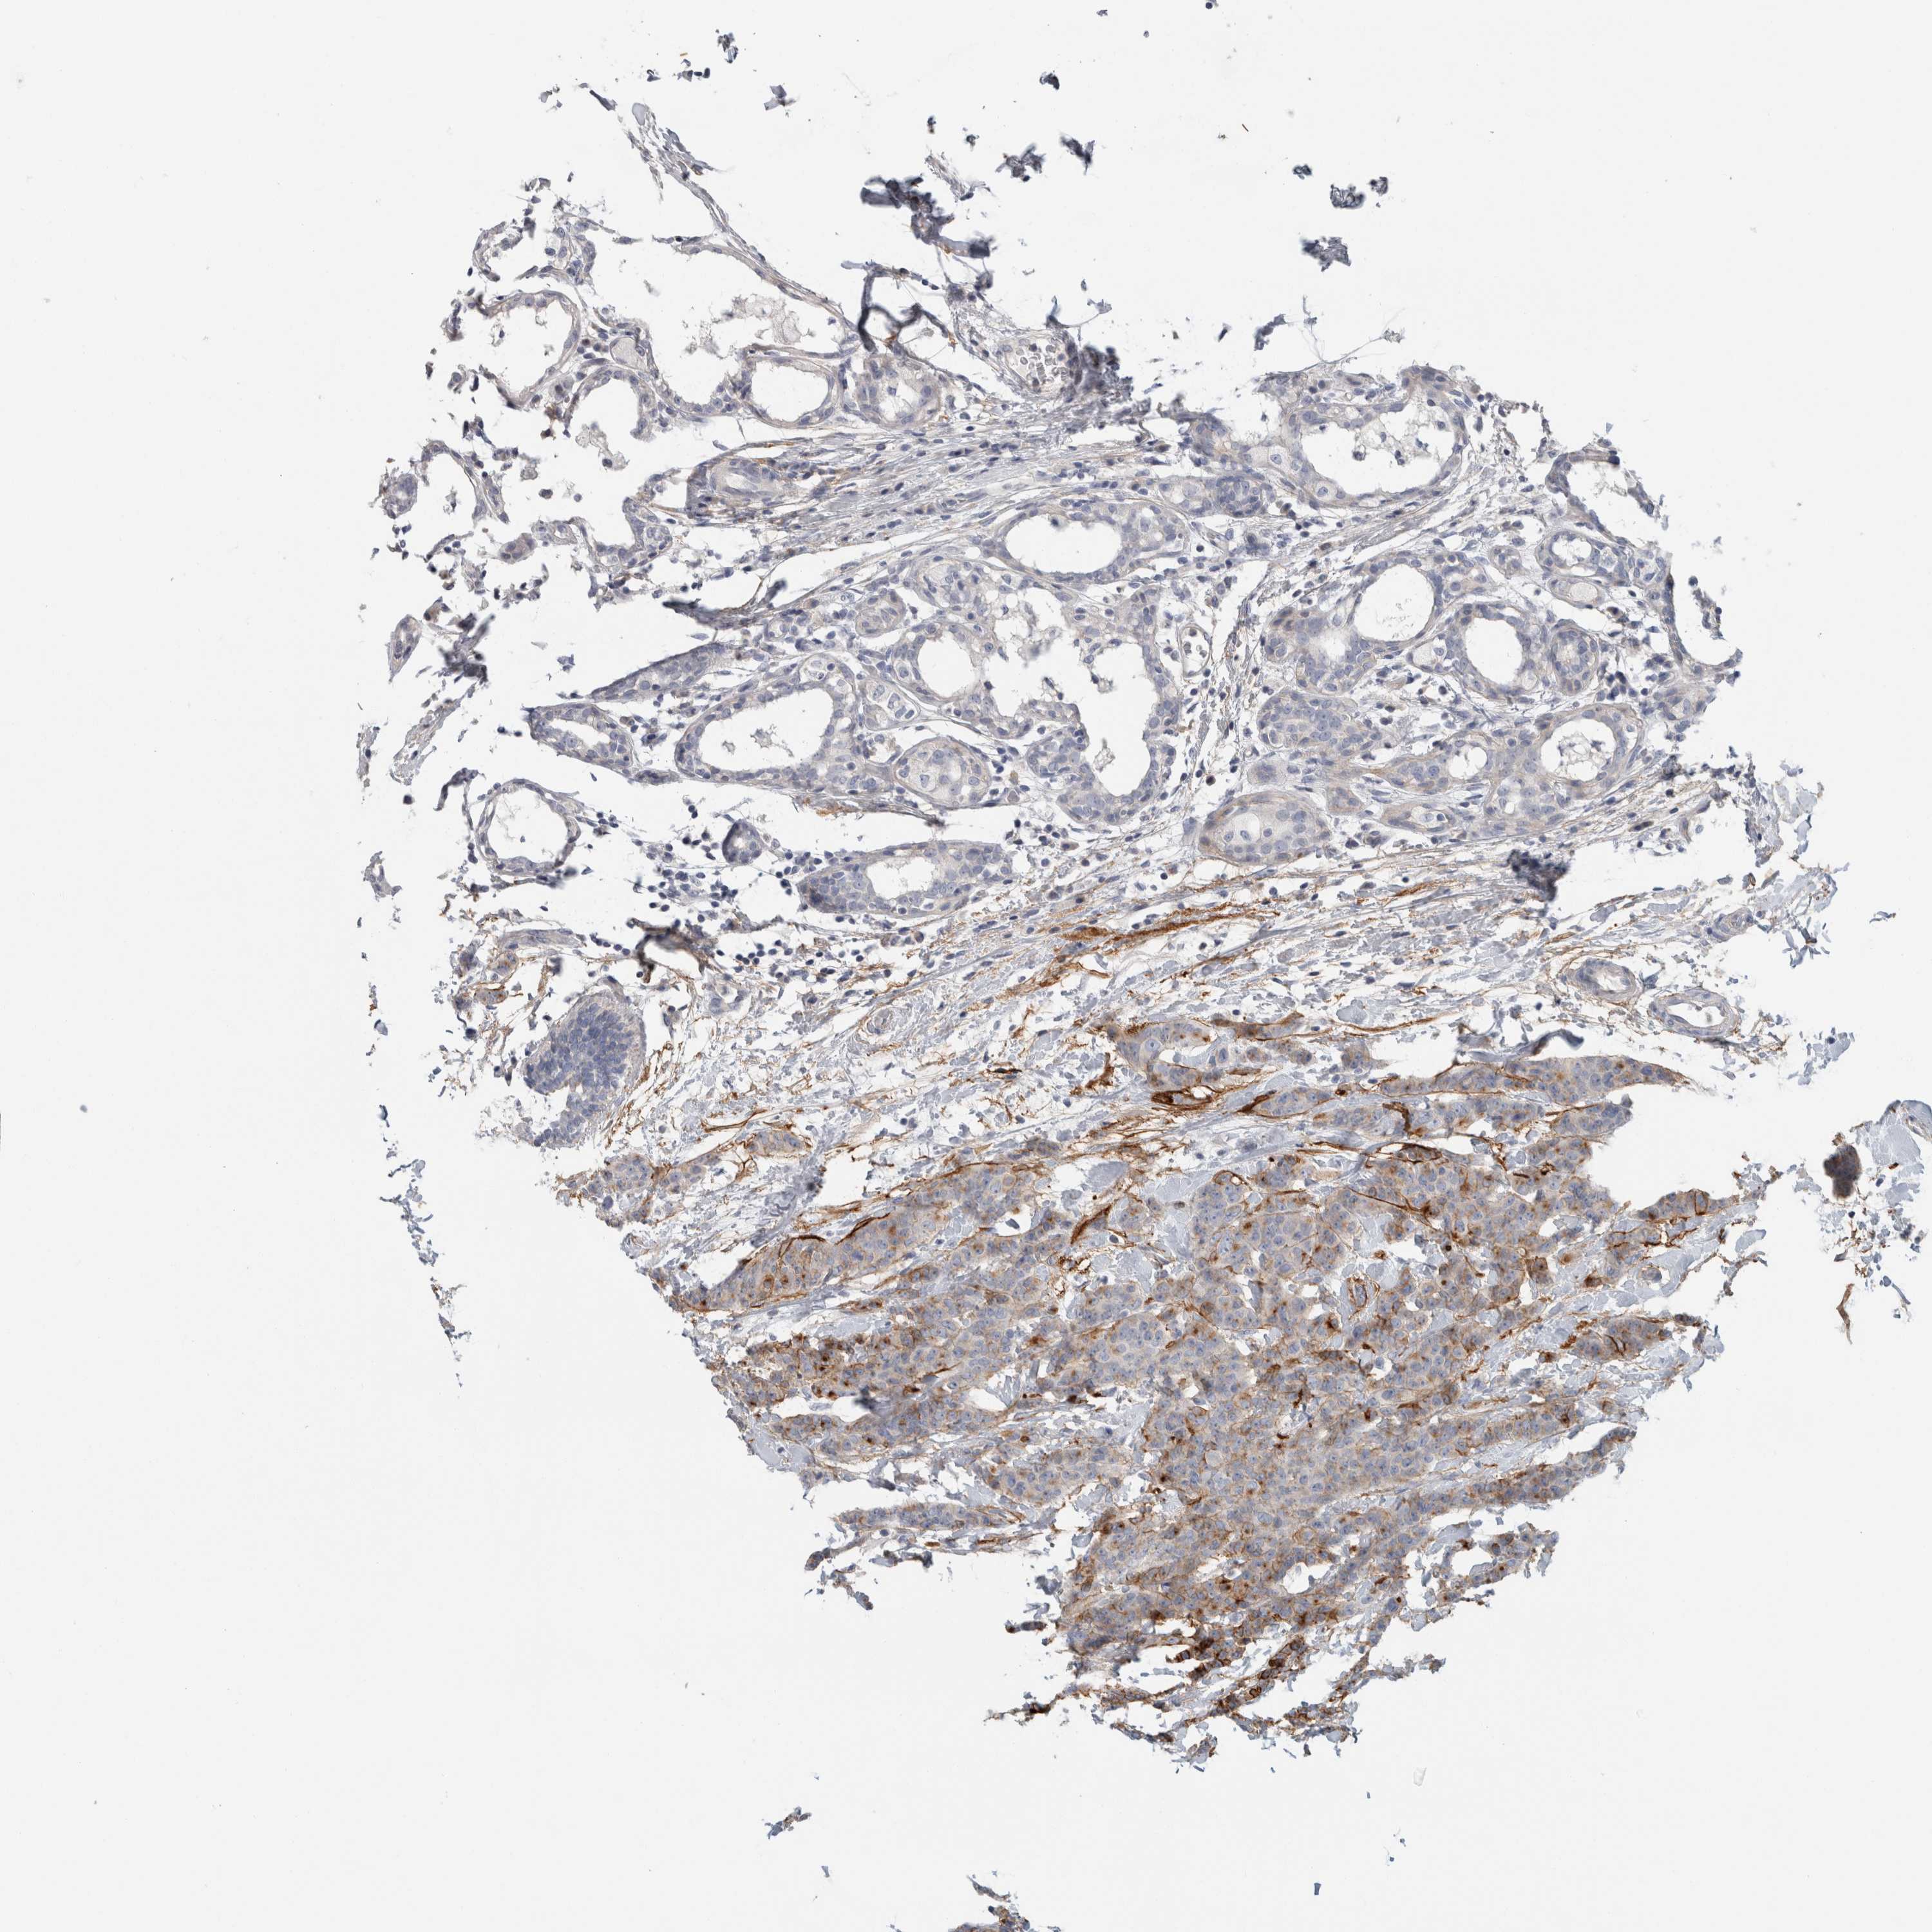

BRCA TCGA BRCA VALIDATION PROTEIN EXPRESSION

ANTIBODIES

AND

VALIDATION